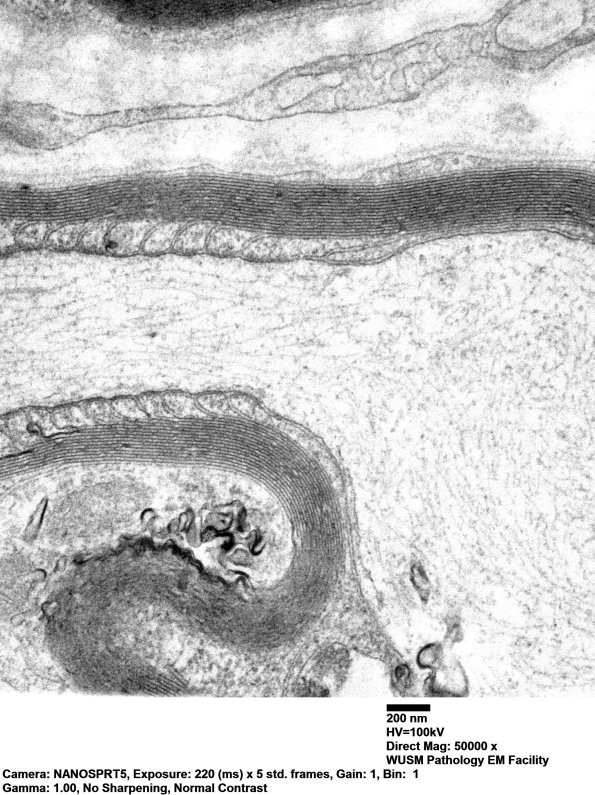

The junction of the paranode and internodal axolemma. (electron micrographs)